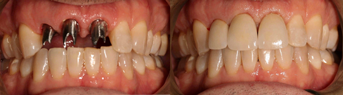

Figure 14 through Figure 18 show a partially dentate patient for whom a fully digital workflow was utilized. This 47-year-old male presented with root blunting and mobility of teeth Nos. 7, 8, and 9 (Figure 14). A thermoplastic clip was attached during the CBCT, and an intraoral scan was taken and superimposed on the CBCT. The case was then planned in the navigation planning software (Figure 15). Once the teeth were extracted, intraoral scanning was performed. The intraoral scan was imported into lab software (Figure 16), and a PMMA milled screw-retained prosthesis was fabricated. The prosthesis was placed the next morning (Figure 17). Two months later, a new intraoral scan was taken to capture the mature soft tissue, and the final milled titanium abutment and restoration were delivered (Figure 18).

Fig 14. Preoperative view of a partially dentate case. Patient with root blunting and grade 3 mobility.

Fig 15. The case was planned using navigation planning software in this same patient.

Fig 16. Virtual design of the provisional prosthesis.

Fig 17. Views of the milled PMMA screw-retained provisional restoration. Note the screw access holes in the incisor edges (left panel). (Images courtesy of Dr. Kim Knoll.)

Fig 18. Placement of the final prosthesis. Milled titanium abutments (left panel) and Emax crowns (right panel). (Images courtesy of Dr. Kim Knoll.)